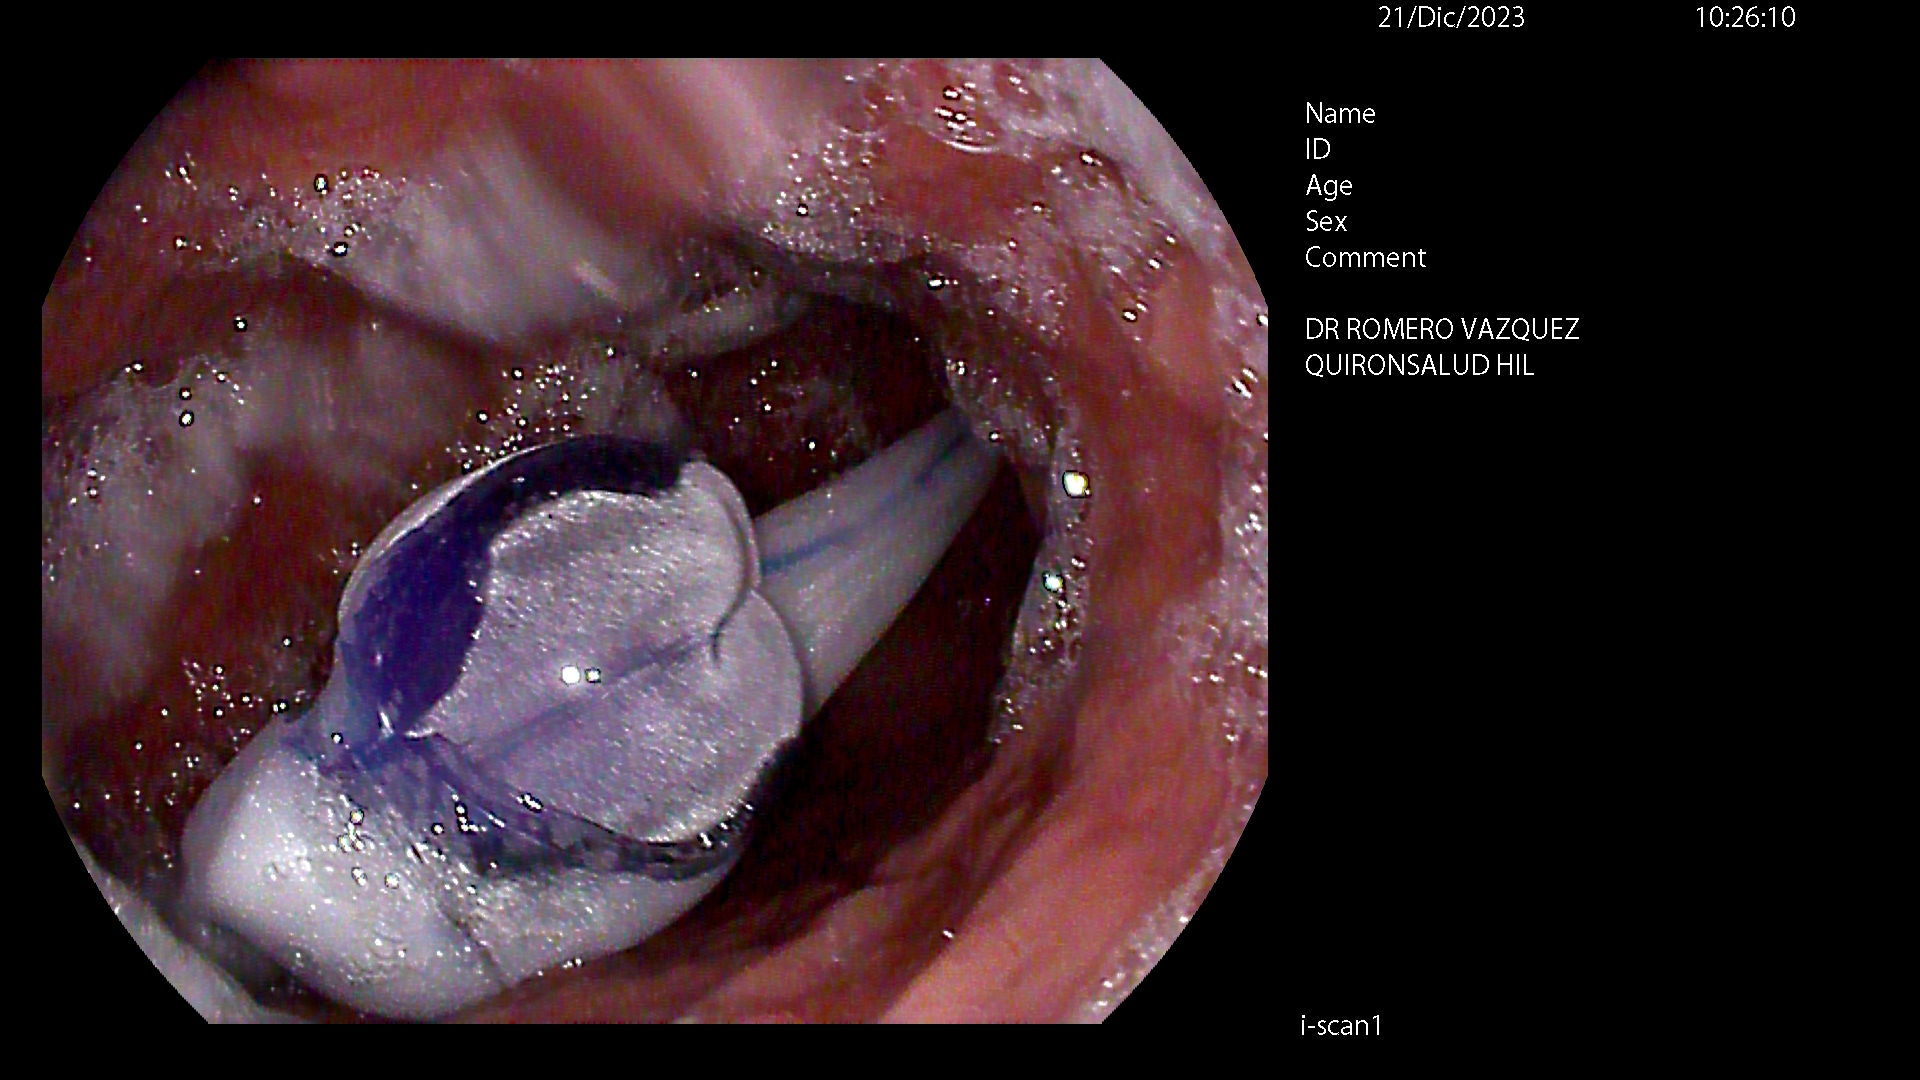

BALÓN INTRAGÁSTRICO

El balón intragástrico es un implante temporal de silicona, que rellenamos con suero, normalmente unos 500-600 cc, con un colorante (azul de metileno) para detectar cualquier posible anomalía futura (pérdida de contenido o rotura), una vez se aloja en el estómago y ocupa una parte importante del mismo. Esto genera dos mecanismos clave para aumentar la saciedad y por ello, perder peso:

Su colocación se realiza en la mayoría de las ocasiones por gastroscopia con sedación profunda administrada y controlada por anestesista, siendo una técnica ambulatoria (no precisa ingreso hospitalario) y su retirada, tras haber cumplido su función a los 6-12 meses, dependiendo de cada caso concreto, por gastroscopia con intubación y anestesista general, para minimizar los posibles inconveniente inherentes a la técnica, igualmente de forma ambulatoria.